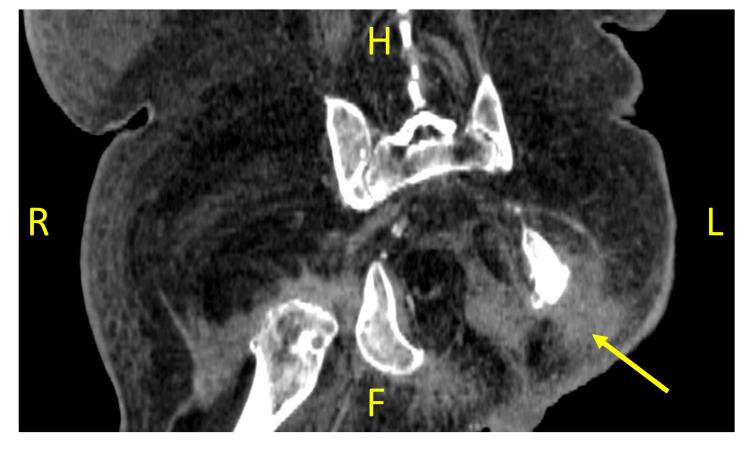

Ertapenem is a carbapenem antibiotic that is typically prescribed in cases of moderate-to-severe infections, especially ones involving abscess formation. We describe the case of an 82-year-old gentleman who presented with osteomyelitis and abscess formation who developed delirium after 15 days of ertapenem treatment. The patient experienced delusions, insomnia, agitation, and disorientation. The patient's mental status improved and returned to his baseline within 48 hours of halting ertapenem treatment. A high index of suspicion is required to identify and treat ertapenem-induced delirium. Withdrawal of ertapenem treatment in such cases usually results in a complete resolution of symptoms.

厄他培南是一种碳青霉烯类抗生素,通常用于治疗中重度感染,尤其是伴有脓肿形成的感染。我们描述了一位82岁男性患者的病例,该患者患有骨髓炎并伴有脓肿形成,在接受厄他培南治疗15天后出现谵妄。患者出现妄想、失眠、躁动和定向障碍。在停止厄他培南治疗后的48小时内,患者的精神状态有所改善并恢复到基线水平。识别和治疗厄他培南引起的谵妄需要高度的怀疑指数。在此类病例中停用厄他培南治疗通常会使症状完全缓解。